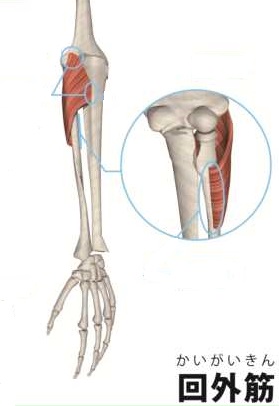

総指伸筋、回外筋部に圧痛あり、その筋をアキュ、マイオを使い施術

総指伸筋、回外筋部に圧痛あり、その筋をアキュ、マイオを使い施術